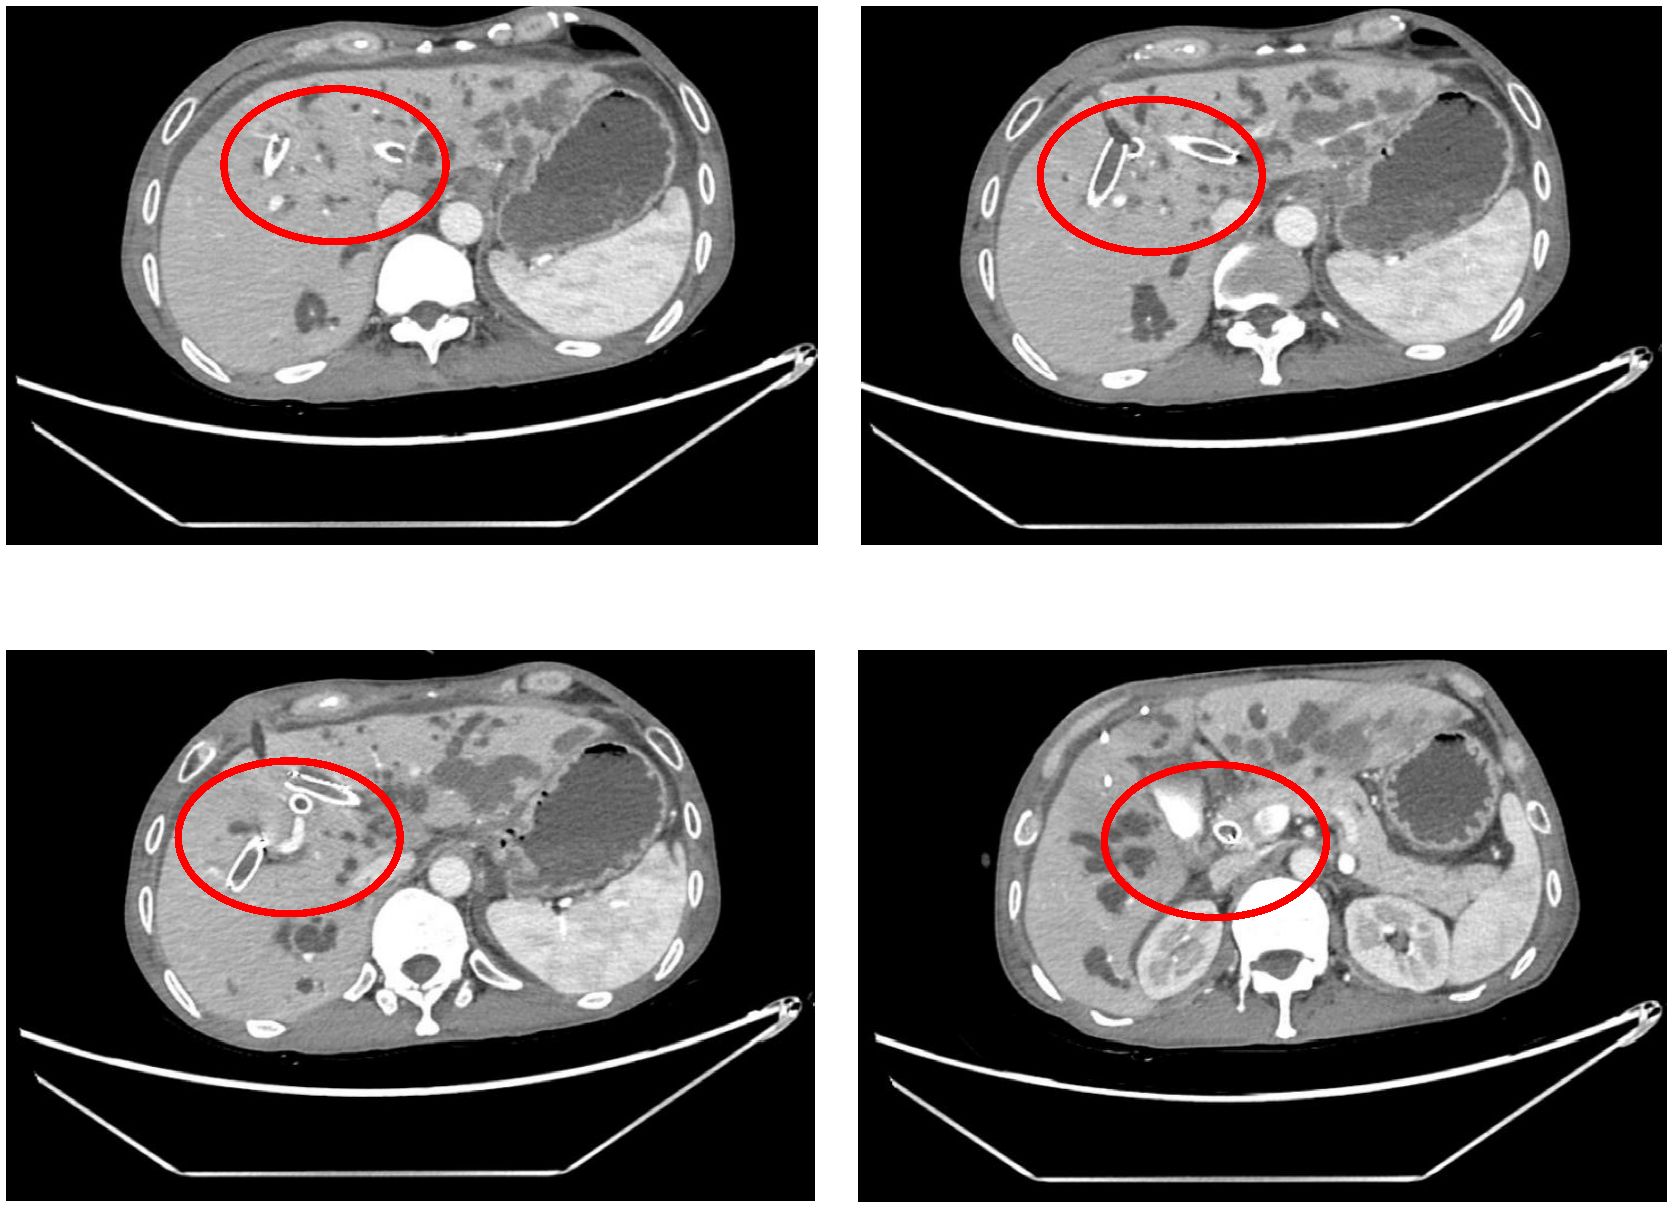

The procedure time was 239 minutes. Jaundice resolved within several days, with total and direct bilirubin levels decreasing to 215.4 μmol/L and 176.4 μmol/L, respectively, within one week (Figure 2). No post-procedure-related adverse events occurred. The patient’s bilirubin decreased by 60% within one week after the procedure compared with the preoperative value, indicating clinical success. Post-procedure CT (Figure 3) at one week showed that bilateral hepatic duct drainage was smooth. The hospital stay was 5 days (ICU stay: 0 days). Palliative adjuvant therapy commenced three weeks post-procedure. During the four-month follow-up period, no reintervention (like another PTBD or surgery) was required.

Supplementary Figure 1 | Computed tomography showed advanced intrahepatic cholangiocarcinoma, hilar bile duct invasion, and radical surgery is not possible. The patient's common bile duct, left, right anterior, and right posterior hepatic ducts were obstructed.